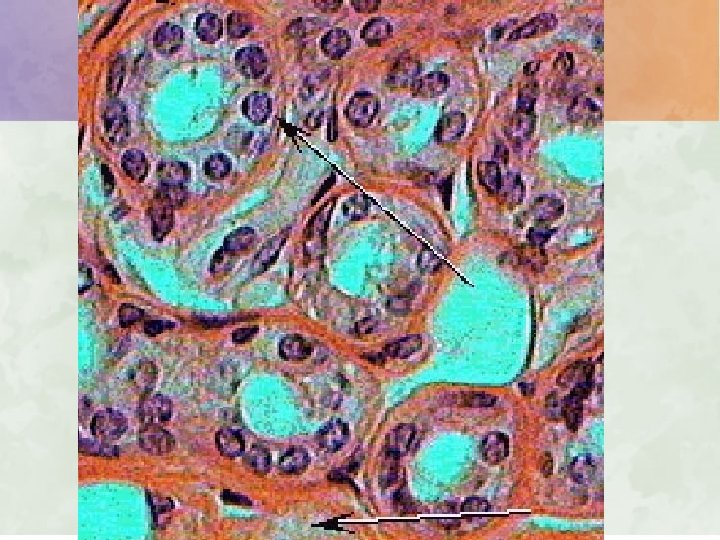

Epithelial tissue • Func – cells form a continuous layer covering internal and external body surfaces, provide protection, produce secretions (digestive juices, hormones, perspiration), and regulate the passage of materials across them.

Epithelial tissue – char. and location • A – Covering and lining tissue – cells can be stratified (layered), ciliated or keratinized (hard, nonliving substance. ) – 1. Squamous epithelial cells • Are flat, irregularly shaped cells. • Line the heart, blood and lymphatic vessels, body cavities, and alveoli of the lungs. • Outer layer of skin consists of stratified squamous epithelia cells. These protect the body against microbial invasion.

Epithelial tissue – char. and location – 2. Cuboidal epithelial cells • Cube-shaped cells line the kidney tubules and cover ovaries and secretory parts of certain glands. – 3. Columnar epithelial cells • Are elongated, w/the nucleus generally near the bottom and often ciliated on the outer surface. • Line ducts, digestive tract, parts of the respiratory tract, and glands.

Epithelial tissue – char. and location • B. Glandular or secretory tissue – cells are specialized to secrete matl’s such as digestive juices, hormones, milk, perspiration, and wax. They are columnar or cuboidal shape. 1. Endocrine gland cells – Form ductless glands which secrete their substances (hormones) directly into the bloodstream.

Epithelial tissue – char. and location – 2. Exocrine gland cells • Cells secrete their substances into ducts. Ex. Mammary glands, sweat glands, and salivary glands.